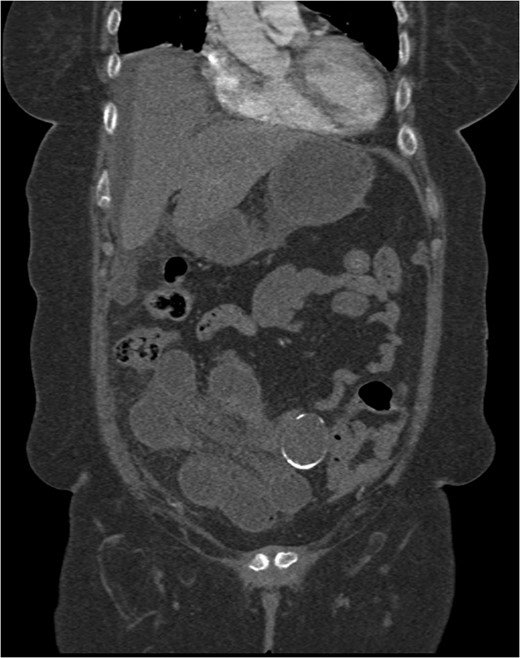

A 74-year-old female, with a background history of hypertension and hypothyroidism, presented to the emergency department with a 6-h history of sudden onset generalized abdominal pain. The pain was colicky in nature, associated with nausea and refractory to analgesia. Examination revealed tenderness in the right upper quadrant and epigastrium. Blood tests were normal except for a mild neutrophilia (7.5 × 109/l) and lactate of 2.5 mmol/l. A computed tomography (CT) scan of her abdomen and pelvis was performed which showed abnormal loops of small bowel along the right side of the abdomen with mesenteric fat stranding. A partially calcified structure was noted lying medial to the loops of bowel (Figs 1 and 2). The patient proceeded to have an explorative laparotomy performed. Intraoperative findings revealed an ischaemic loop of small bowel wrapped around a mass in the mesentery adjacent to the sigmoid colon (Fig. 3). The patient underwent a partial small bowel resection with primary anastomosis and en-bloc resection of the mass with the formation of an end colostomy. The final histological revealed a 6 × 4 × 4 cm cystic colonic duplication cyst separate but adjacent to the sigmoid colon. The inner lining of the cyst revealed mucinous epithelium, with mucin contained within. The wall of the cyst was sclerotic with occasional lymphoid aggregates, smooth muscle and neurovascular bundles (Fig. 4). The patient made a good recovery and was discharged home.

Coronal CT scan showing a partially calcified structure adjacent to loops of small bowel.